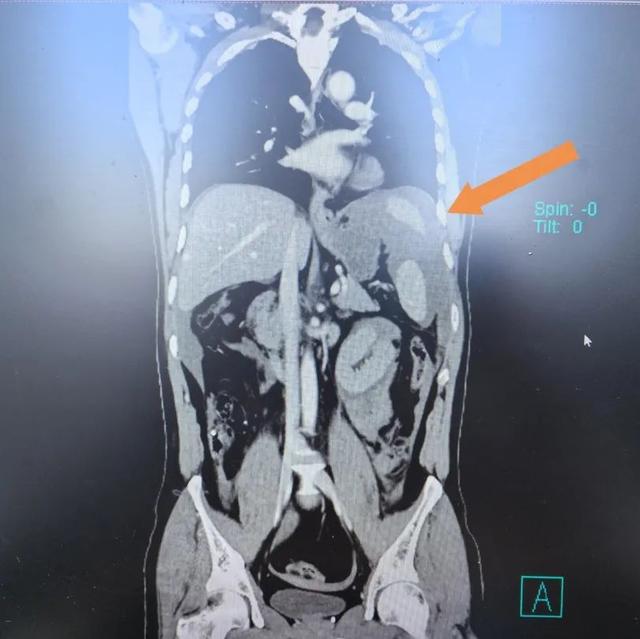

▲患者CT影像

遂即刻完善胸腹部增强CT,明确患者存在肠管损伤、肠系膜损伤出血,即刻转入手术室准备手术。